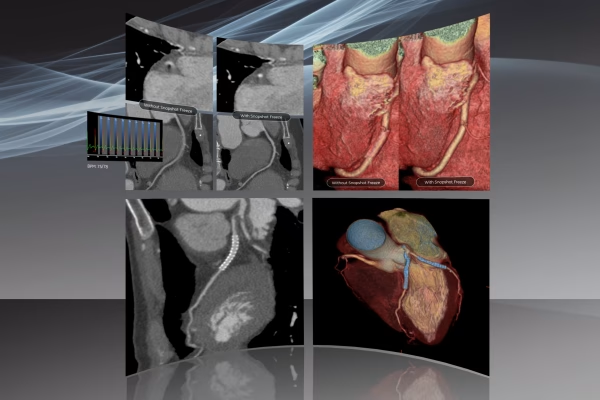

Notre service d’Imagerie Médicale et Radiologie Interventionnelle, un pilier essentiel de notre approche diagnostique. Avec une expertise avancée et une technologie de pointe, nous offrons une imagerie de haute précision pour éclairer votre parcours médical. Notre équipe de spécialistes dévoués s’engage à fournir des diagnostics fiables et des soins personnalisés, en mettant l’accent sur votre bien-être et votre satisfaction. Vous pouvez compter sur nous pour une expérience professionnelle et des résultats médicaux de qualité supérieure.

IRM GE Signa Explorer 1.5T

Scanner GE Optima CT520